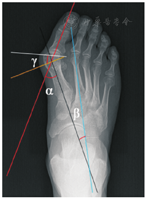

于患者X线片分别画出近节趾骨轴线、第一跖骨轴线、第二跖骨轴线、第一趾骨远端实际关节面连线,测量HVA、IMA和DMAA。见图1。先由1位足踝专科主任医师对每张X线片上的解剖标志予以标出,再由4名足踝专科住院医师使用测角仪对X线片完成测量,测量结果取平均值。

外翻角(HVA)、跖间角(IMA)、跖骨远端关节面夹角(DMAA)的测量 红线为近节趾骨轴线;黑线为第一跖骨轴线;蓝线为第二跖骨轴线;白线为第一跖趾关节实际关节面连线;黄线为第一跖骨轴线的垂线;∠α为HVA;∠β为IMA;∠γ为DMAA

外翻角(HVA)、跖间角(IMA)、跖骨远端关节面夹角(DMAA)的测量 红线为近节趾骨轴线;黑线为第一跖骨轴线;蓝线为第二跖骨轴线;白线为第一跖趾关节实际关节面连线;黄线为第一跖骨轴线的垂线;∠α为HVA;∠β为IMA;∠γ为DMAA将扫描后获得的CT连续断层图像数据以DICOM 3.0数据格式导入Materialise Mimics 19. 01(Materialise,比利时)软件中。根据不同的灰度值进行分割,提取跖骨和趾骨边界的轮廓信息区,对带有不同阈值的背景、软组织和骨组织进行阈值分割(Thresholding),设定阈值最小为242、最大2 185,使用区域增长(regional growth),将离散的体素去除,把骨性结构分割出来(图2A)。对分割出来的第一跖骨、第二跖骨、近节趾骨所对应的每层蒙板进行多层编辑(添加、删除、填充等)操作后,进行3D重建(calculate 3D from mask),重建第一跖骨、第二跖骨、近节趾骨3D模型(图2B)。